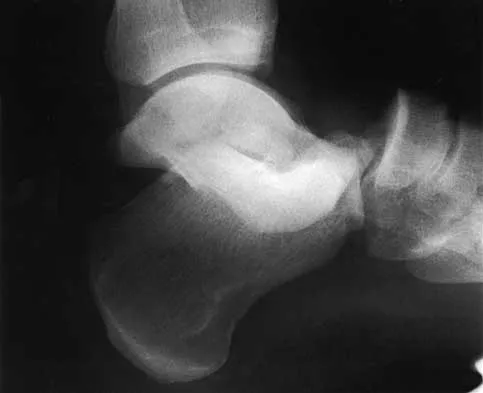

Figure 7 shows the CT scan of a 25-year-old soccer player who has had posterior ankle pain with plantar flexion for the past 2 years. Immobilization has failed to provide relief. He is ambulatory. Management should consist of

Explanation

An os trigonum is usually asymptomatic, but this accessory bone has been associated with persistent posterior ankle pain, which has been described as os trigonum syndrome. This usually affects athletes and ballerinas. Forced plantar flexion leads to impingement of the os trigonum against the posterior tibial plafond, and flexor hallucis tendinitis may develop. It may be difficult to differentiate a fractured trigonal process from the os trigonum. MRI may reveal bone marrow edema that may aid in the diagnosis of os trigonum syndrome. Steroid injections may lead to tendon rupture. The results of excision of a symptomatic os trigonum through a posteromedial or lateral approach are favorable, with a rapid return to full function. The main complication of this procedure is sural nerve injury with a lateral approach. Hedrick MR, McBryde AM: Posterior ankle impingement. Foot Ankle Int 1994;15:2-8.